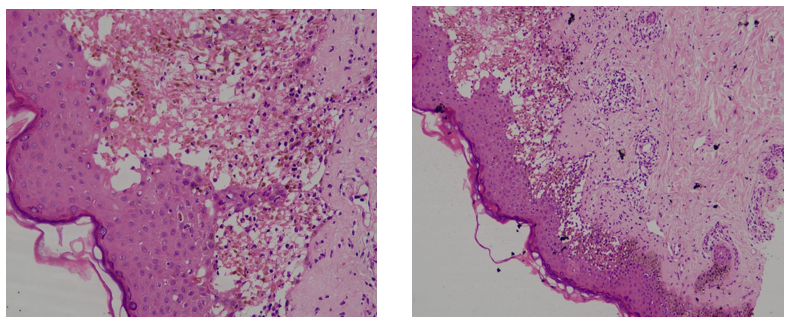

There is a presence of neutrophils, scattered melanophages, necrotic keratinocytes, and extensive death of keratinocytes along with basal vacuolar degeneration. Lymphocytic and neutrophilic exocytosis is also observed.

Fig.2. Lesional bulla, Perilesional area: - Features are separation of epidermis from the dermis, presence of neutrophils, scattered melanophages, necrotic keratinocytes, and extensive death of keratinocytes along with basal vacuolar degeneration, favoring Steven-Johnson-Syndrome